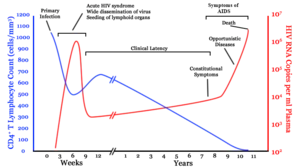

There are three main stages of HIV infection: acute infection, clinical latency, and AIDS.[1][30]

Acute infection

The initial period following infection with HIV is called acute HIV, primary HIV or acute retroviral syndrome.[30][31] Many individuals develop an illness-like influenza, mononucleosis or glandular fever 2–4 weeks after exposure while others have no significant symptoms.[32][33] Symptoms occur in 40–90% of cases and most commonly include fever, large tender lymph nodes, throat inflammation, a rash, headache, tiredness, and/or sores of the mouth and genitals.[31][33] The rash, which occurs in 20–50% of cases, presents itself on the trunk and is maculopapular, classically.[34] Some people also develop opportunistic infections at this stage.[31] Gastrointestinal symptoms, such as vomiting or diarrhea may occur.[33] Neurological symptoms of peripheral neuropathy or Guillain–Barré syndrome also occur.[33] The duration of the symptoms varies, but is usually one or two weeks.[33]

Clinical latency

The initial symptoms are followed by a stage called clinical latency, asymptomatic HIV, or chronic HIV.[1] Without treatment, this second stage of the natural history of HIV infection can last from about three years[35] to over 20 years[36] (on average, about eight years).[37] While typically there are few or no symptoms at first, near the end of this stage many people experience fever, weight loss, gastrointestinal problems and muscle pains.[1] Between 50% and 70% of people also develop persistent generalized lymphadenopathy, characterized by unexplained, non-painful enlargement of more than one group of lymph nodes (other than in the groin) for over three to six months.[30]

Although most HIV-1 infected individuals have a detectable viral load and in the absence of treatment will eventually progress to AIDS, a small proportion (about 5%) retain high levels of CD4+ T cells (T helper cells) without antiretroviral therapy for more than five years.[33][38] These individuals are classified as "HIV controllers" or long-term nonprogressors (LTNP).[38] Another group consists of those who maintain a low or undetectable viral load without anti-retroviral treatment, known as "elite controllers" or "elite suppressors". They represent approximately 1 in 300 infected persons.[39]

Acquired immunodeficiency syndrome

Acquired immunodeficiency syndrome (AIDS) is defined as an HIV infection with either a CD4+ T cell count below 200 cells per µL or the occurrence of specific diseases associated with HIV infection.[33] In the absence of specific treatment, around half of people infected with HIV develop AIDS within ten years.[33] The most common initial conditions that alert to the presence of AIDS are pneumocystis pneumonia (40%), cachexia in the form of HIV wasting syndrome (20%), and esophageal candidiasis.[33] Other common signs include recurrent respiratory tract infections.[33]

Pathophysiology

After the virus enters the body, there is a period of rapid viral replication, leading to an abundance of virus in the peripheral blood. During primary infection, the level of HIV may reach several million virus particles per milliliter of blood.[103] This response is accompanied by a marked drop in the number of circulating CD4+ T cells. The acute viremia is almost invariably associated with activation of CD8+ T cells, which kill HIV-infected cells, and subsequently with antibody production, or seroconversion. The CD8+ T cell response is thought to be important in controlling virus levels, which peak and then decline, as the CD4+ T cell counts recover. A good CD8+ T cell response has been linked to slower disease progression and a better prognosis, though it does not eliminate the virus.[104]

Ultimately, HIV causes AIDS by depleting CD4+ T cells. This weakens the immune system and allows opportunistic infections. T cells are essential to the immune response and without them, the body cannot fight infections or kill cancerous cells. The mechanism of CD4+ T cell depletion differs in the acute and chronic phases.[105] During the acute phase, HIV-induced cell lysis and killing of infected cells by CD8+ T cells accounts for CD4+ T cell depletion, although apoptosis may also be a factor. During the chronic phase, the consequences of generalized immune activation coupled with the gradual loss of the ability of the immune system to generate new T cells appear to account for the slow decline in CD4+ T cell numbers.[106]

Although the symptoms of immune deficiency characteristic of AIDS do not appear for years after a person is infected, the bulk of CD4+ T cell loss occurs during the first weeks of infection, especially in the intestinal mucosa, which harbors the majority of the lymphocytes found in the body.[107] The reason for the preferential loss of mucosal CD4+ T cells is that the majority of mucosal CD4+ T cells express the CCR5 protein which HIV uses as a co-receptor to gain access to the cells, whereas only a small fraction of CD4+ T cells in the bloodstream do so.[108] A specific genetic change that alters the CCR5 protein when present in both chromosomes very effectively prevents HIV-1 infection.[109]

HIV seeks out and destroys CCR5 expressing CD4+ T cells during acute infection.[110] A vigorous immune response eventually controls the infection and initiates the clinically latent phase. CD4+ T cells in mucosal tissues remain particularly affected.[110] Continuous HIV replication causes a state of generalized immune activation persisting throughout the chronic phase.[111] Immune activation, which is reflected by the increased activation state of immune cells and release of pro-inflammatory cytokines, results from the activity of several HIV gene products and the immune response to ongoing HIV replication. It is also linked to the breakdown of the immune surveillance system of the gastrointestinal mucosal barrier caused by the depletion of mucosal CD4+ T cells during the acute phase of disease.[112]